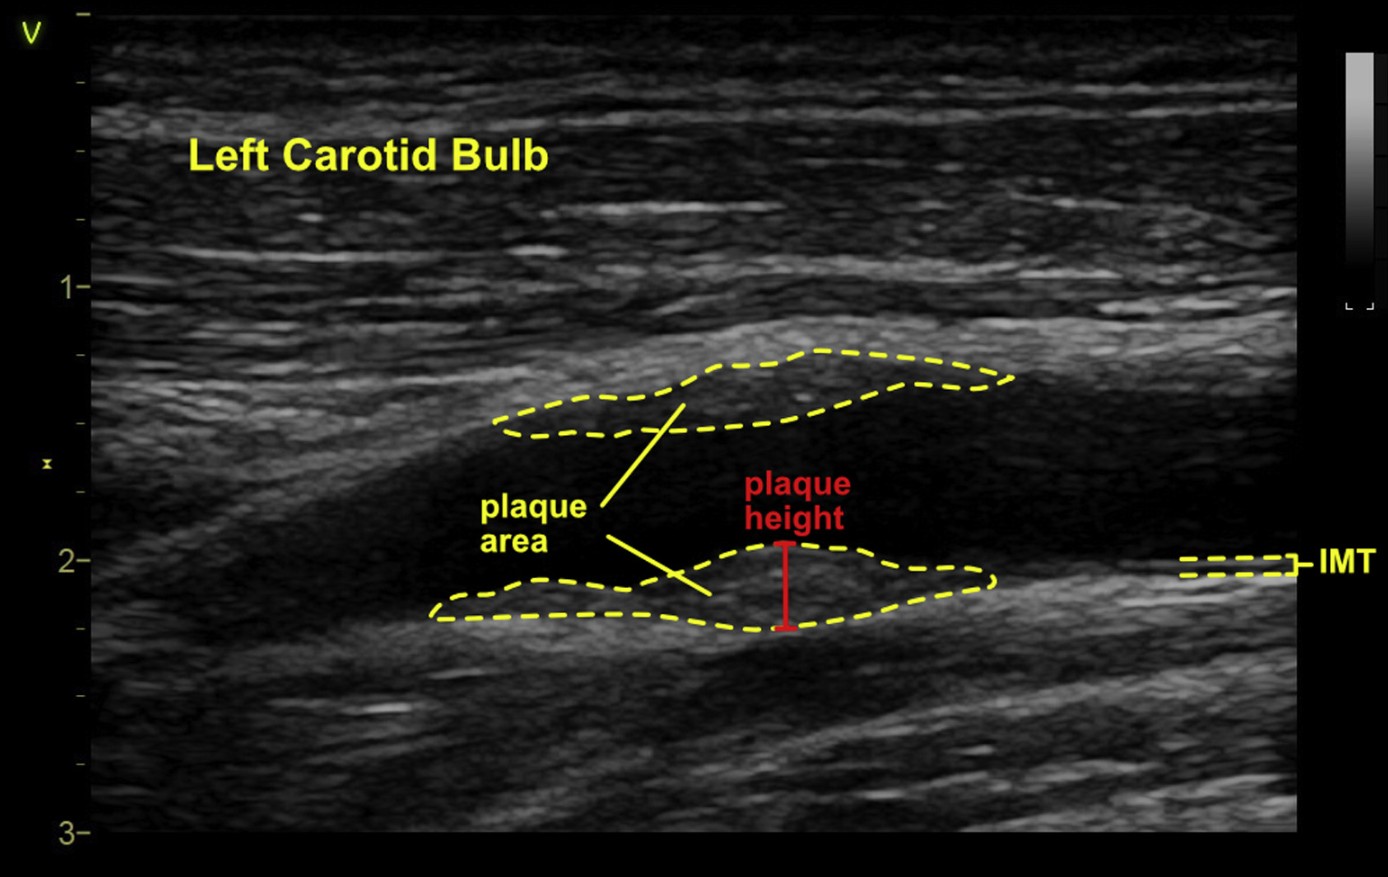

It is recognized that in some centers, repeat evaluation of CIMT in the absence of plaque is considered if CIMT is >75th percentile for age, race, and gender.20 Despite the lack of evidence surrounding the frequency of repeat testing, an interval for repeat testing of 2-5 years has been utilized in population studies, although published evidence suggests that more frequent CIMT measurements could increase the precision of the assessment of CIMT progression.21 Methodological limitations of this study notwithstanding, our expert panel recommends against serial CIMT measurements for CVD risk stratification especially when not meeting the threshold for diffuse plaque (≥1.5 mm). We recognized that based on limited or anecdotal evidence, there may be value in serial CIMT measurements in the hands of some experts for research,22,23, monitoring of progression or regression in specific cases 24,25, and as a potential tool to alter patient behavior.26 Additionally, it is possible that over time, an individual patient may have a CIMT value that has increased to ≥1.5 mm, signifying the development of diffuse atherosclerotic plaque by our definition; however the clinical utility of such long term CIMT monitoring is not yet established.We have suggested that a CIMT ≥1.5 mm be considered a clinically significant lesion for patients less than 65 years of age. The thickness (also known as height in the long axis view) of a carotid arterial plaque lesion, whether it is protuberant or diffuse, was chosen as the initial measure to define plaque because of its widespread availability and because this variable can be measured in both protuberant or diffuse types of plaque lesions (Figure 1). Additional quantification techniques such as area and volume apply mostly to protuberant-type plaque lesions, and are difficult to define in atherosclerotic lesions that are diffusely layered along the intimal wall. Such lesions may be focal or diffuse wall calcification layered in a concentric or eccentric manner and may represent atherosclerotic or non-atherosclerotic processes. Accordingly, our panel suggests the grading system for both protuberant and diffuse plaque lesions as described in Figure 1.Figure 1 Plaque Grading Consensus: carotid medial thickening and intimal plaque. Carotid intimal-medial thickening is thought to involve thickening of the medial layer whereas plaque is thought to be an intimal process as suggested in this schematic. However, diffuse intimal thickening may also occur that is difficult to distinguish from a medial process, and though not protuberant, eccentric or concentric thickening of 1.5 mm or greater is suggested to be a plaque equivalent by this system.The grading system does not reflect the degree of vesselocclusion but attempts to standardize the size of an individual plaque lesion for the purpose of comparison across studies. It is important to note that Grade I characterization applies only to small protuberant types of plaque lesions. This is because, though ultrasound can now resolve such small protuberant lesions, if the plaque is non-protuberant (diffuse or eccentric) and less than 1.5 mm in thickness, it is currently not possible to distinguish whether this is entirely due to medial thickening or is intimal. However at a CIMT value of 1.5 mm or greater (Grades II and III), this framework attributes the thickness to be due to diffuse atherosclerotic plaque (mostly intimal rather than medial) and is thus considered a plaque equivalent. The Grades II and III measurements are applied to obviously protuberant plaque in the same manner for simplicity (Figure 1).Recommendation #4: We recommend against serial carotid intima-media thickness (CIMT) measurements in an asymptomatic patient. Repeat measurements are not recommended unless the Grade and (CIMT) meets criteria for diffuse-type plaque (Grades II or III, and CIMT ≥1.5 mm) in which case it is a plaque equivalent.Quantification Methods

Two-dimensional imaging measurements are affected by the imaging plane and can introduce variability into area measurements. Cross-sectional imaging helps mitigate this to an extent. Additionally, judging the extent of plaque, i.e., the area surrounding the maximal plaque thickness can be subjective and hence associated with inherent measurement errors. Other general but important limitations associated with standard 2D imaging of arterial plaque include the operator dependence of this method, variable image quality, out-of-plane registration errors and the time requirement, limiting its use in clinical practice.41 On balance, the writing group concluded that the disadvantages of measuring plaque area outweigh the current limitations of 2D height measurement, and we have not identified this approach as a recommended technique (See recommendations #5 and #6). Figure 2 provides a summary of current 2D methods, including plaque height and area.Figure 2 2D methods of plaque assessment. Two-dimensional methods of quantifying arterial plaque, including plaque area and plaque height. Intimal-medial thickening is also shown for demonstration but is suggested to be measured in the absence of plaque. As demonstrated in this figure, plaque thickness is measured beginning from the adventitial plane (same plane as where CIMT begins). It is recognized that in some cases the plaque may be mostly intimal, appear distinct from the underlying medial layer, and not extend fully to the medial-adventitial border, however the measurement should still begin from this medial-adventitial plane for the purposes of standardization.Application of Carotid Arterial Plaque Imaging in Clinical Practice